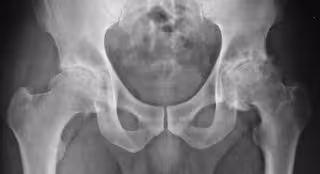

Artrosis - FLICKR/SILVANA CIARDULLO - Archivo